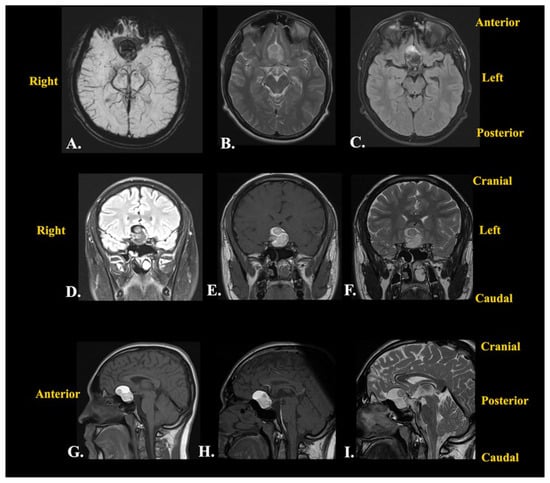

Following this investigation, a brain CT scan was performed to obtain more imagistic details (Figure 4).

Figure 4. Preoperative brain CT scan: (A) native axial sequence; (B) native sagittal sequence; (C) native coronal sequence; (D) contrast-enhanced axial sequence; (E) contrast-enhanced sagittal sequence; (F) contrast-enhanced coronal sequence.

The results depicted a tumoral mass, well delimited and localized at the median line in the suprasellar cistern and without a surrounding edema, without contrast enhancement, and with intrasellar prolabation. The lesion had a slightly inhomogeneous structure given the presence of areas with high densities (−27 UH, compared to −116 UH), corresponding to microcalcifications/hemorrhages/saponification of fats.

Subsequent cerebral angiography excluded any intracranial vascular malformations and highlighted the relationships with the neighboring blood vessels. An intracranial non-enhancing compressive mass lesion was determined, with a bilateral A1 segment of the anterior cerebral artery’s ascension (a positive “vault sign”).